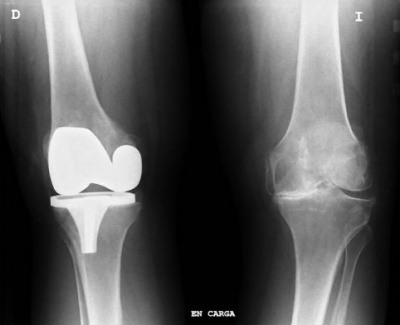

L'artroprotesi consiste un un intervento di protesi articolare e trova applicazione quando l'articolazione del ginocchio risulta rigida e compromessa in modo irrimediabile, rappresentando il trattamento definitivo dell’artrosi del ginocchio. Tale trattamento chirurgico consiste nell’asportazione di tutta la cartilagine articolare e di una sottile fetta di osso sub-condrale con contestuale impianto di componenti protesiche costituite da materiale inerte come metallo e plastica-polietilene.

In base alla tipologia, esistono varie tipologie di protesi :

monocompartimentali per le artrosi omonime,

bicompartimentali e tricompartimentali

con componente rotulea

Tutte le protesi possono essere fissate nell’osso con con l’ausilio di cemento acrilico ovvero con meccanismi ad incastro perfetto (press-fit). L'avanzare delle tecnologie in ambito medico ha introdotto una nuova tecnica chirurgica di impianto di protesi chiamata CAOS (computer assisted orthopaedic surgery) con la quale il posizionamento e l’allineamento delle componenti vengono migliorate sensibilmente rispetto alle metodologie tradizionali.